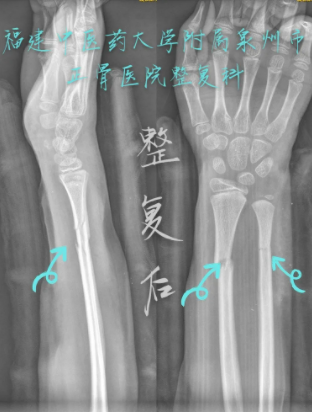

元元X光拍摄照片 — 整复前(正骨医院供图)

元元X光拍摄照片 — 整复后(正骨医院供图)